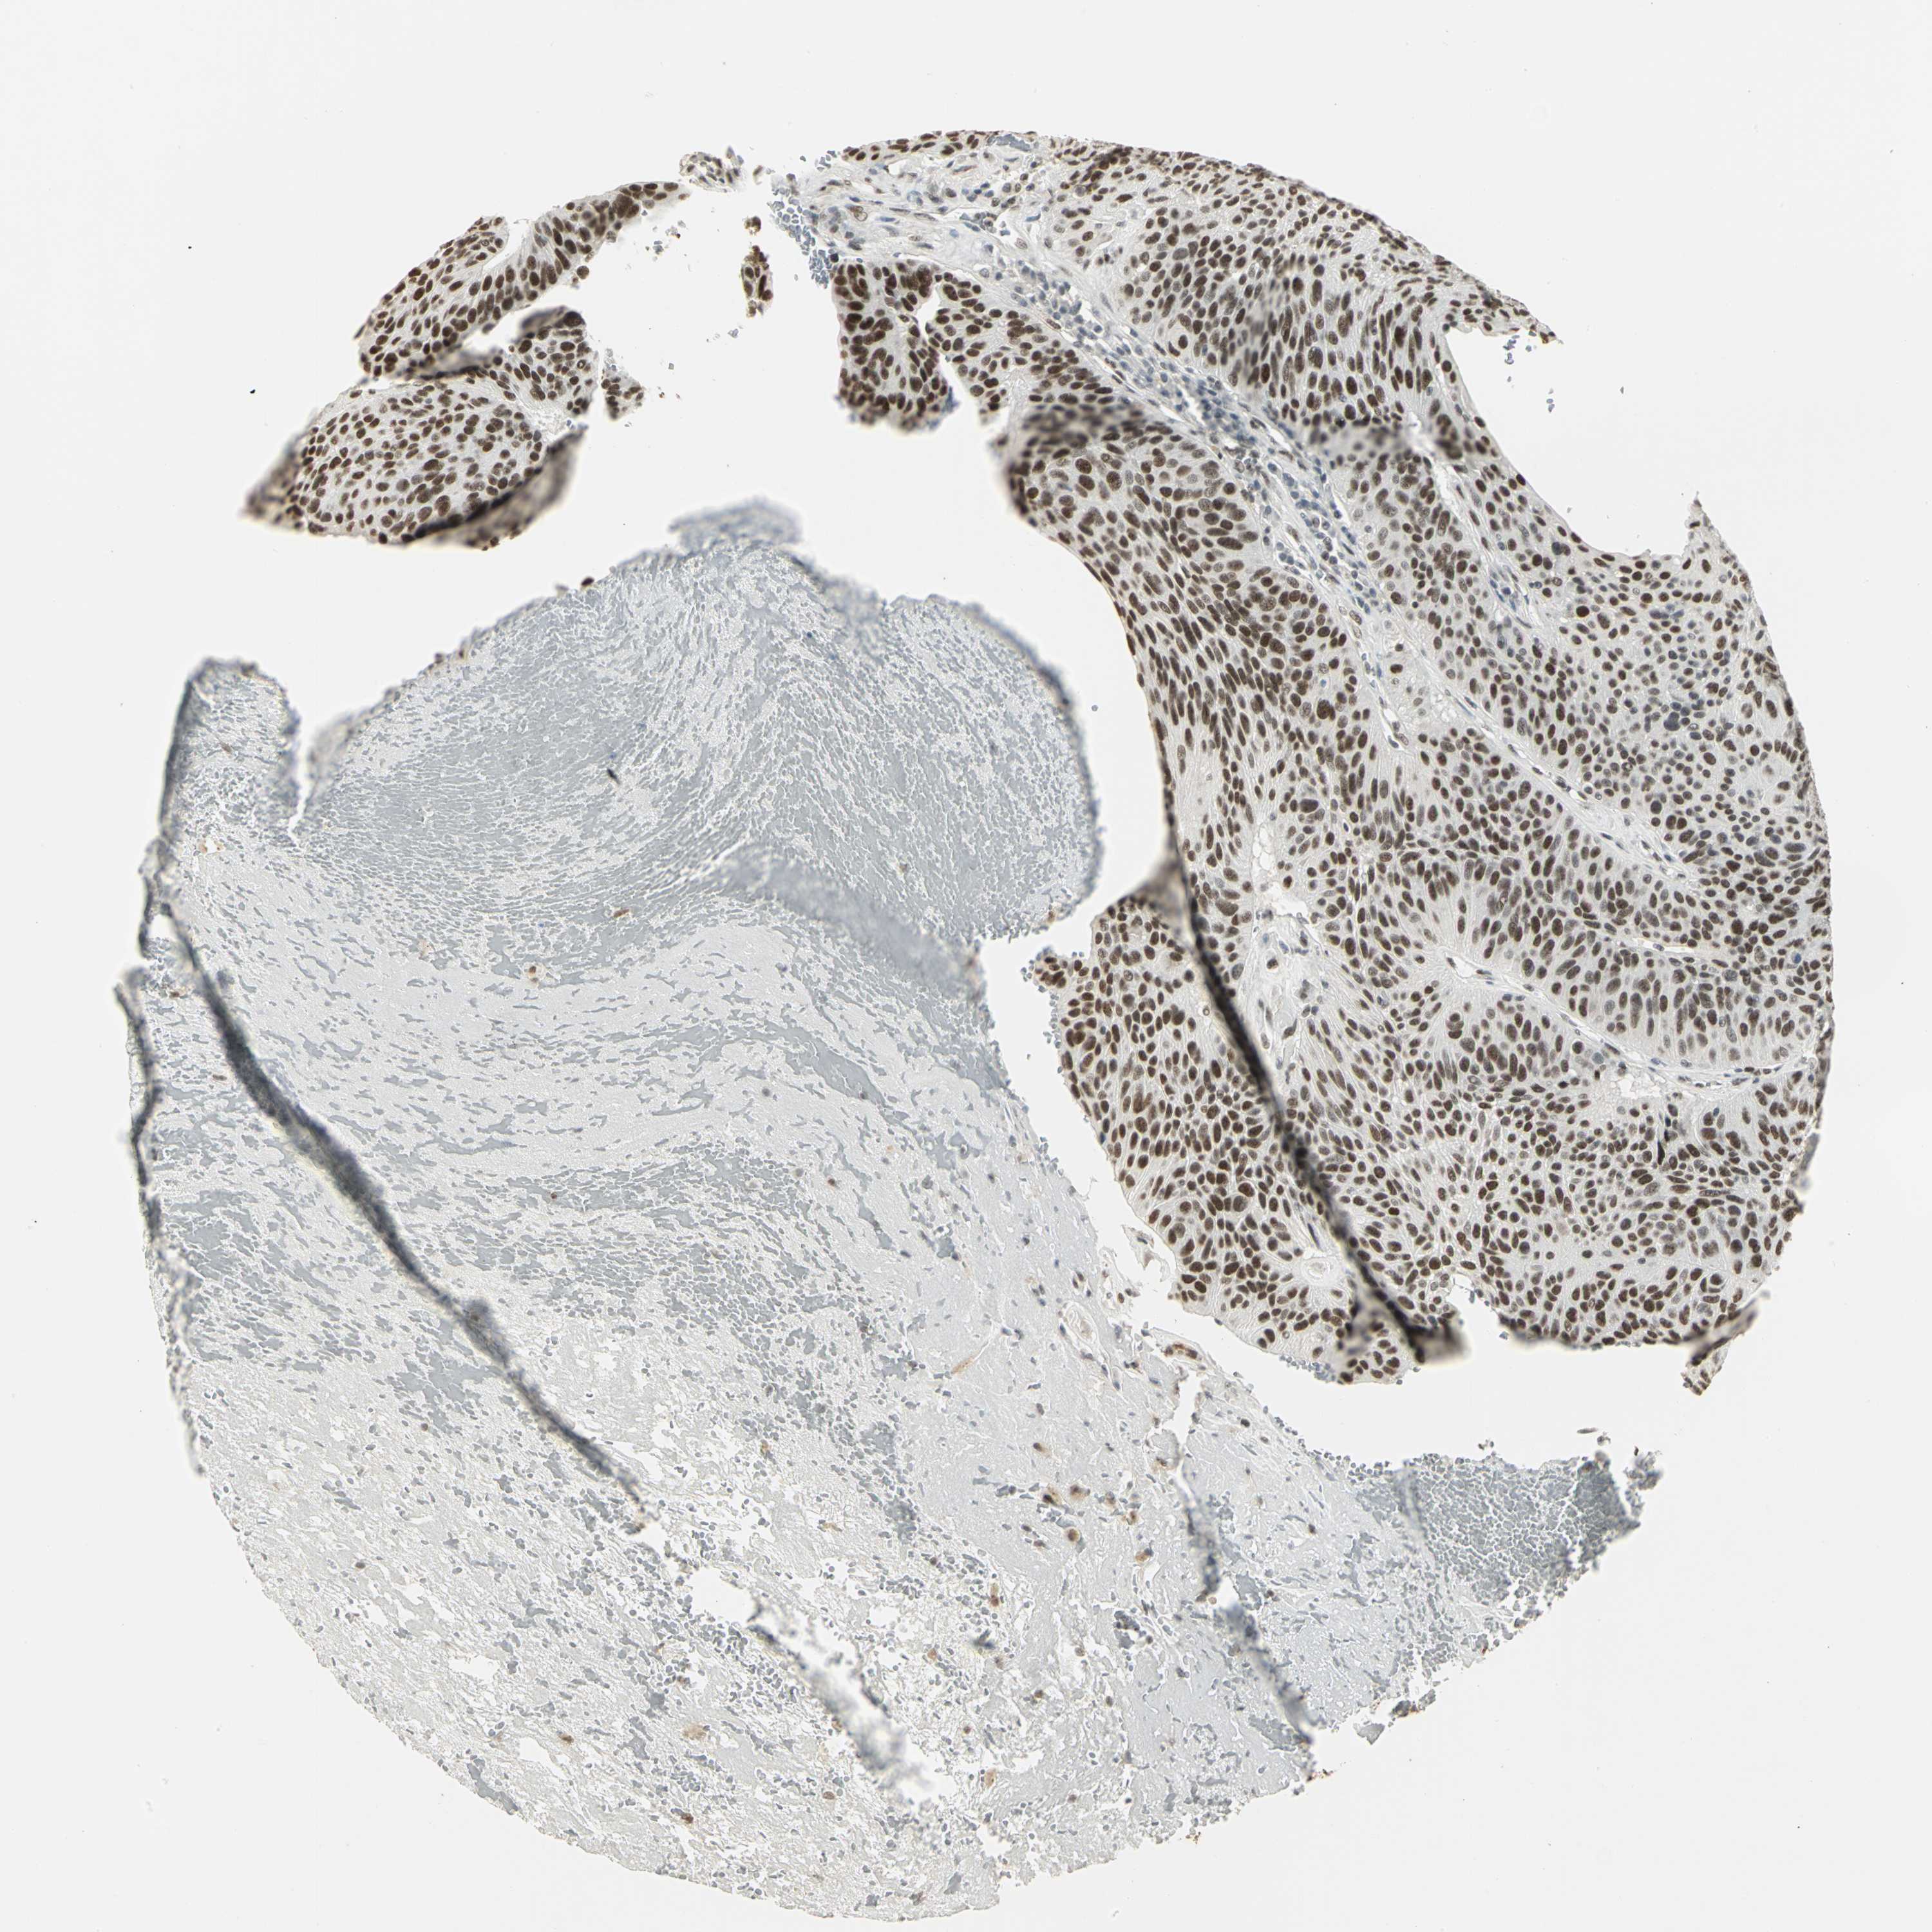

UROTHELIAL CANCER - Protein expressioni

A mouse-over function shows sample information and annotation data. Click on an image to view it in a full screen mode. Samples can be filtered based on level of antibody staining by selecting one or several of the following categories: high, medium, low and not detected. The assay and annotation is described here.

Antibody stainingi

Antibody staining in the annotated cell types in the current human tissue is reported as not detected, low, medium, or high, based on conventional immunohistochemistry profiling in selected tissues. This score is based on the combination of the staining intensity and fraction of stained cells.

Each image is clickable and will lead to virtual microscopy that enables deeper exploration of all samples and also displays staining intensity scores, fraction scores and subcellular localization as well as patient and tissue information for each sample.

Antibody HPA004902

Antibody CAB001973

Staining

High

Medium

Low

Not detected

Intensity

Strong

Moderate

Weak

Negative

Quantity

>75%

75%-25%

<25%

None

Location

Nuclear

Cytoplasmic/membranous

Cytoplasmic/membranous,nuclear

Urothelial carcinoma, High grade

Urothelial carcinoma, Low grade

Adenocarcinoma, NOS